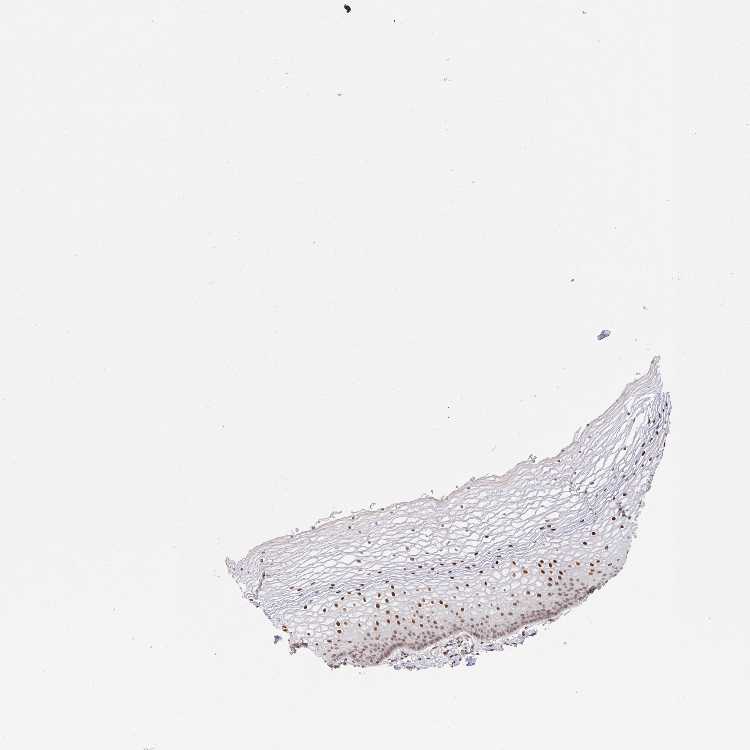

VAGINA - Antibody stainingi

Antibody staining in the annotated cell types in the current human tissue is reported as not detected, low, medium, or high, based on conventional immunohistochemistry profiling in selected tissues. This score is based on the combination of the staining intensity and fraction of stained cells.

Each image is clickable and will lead to virtual microscopy that enables deeper exploration of all samples and also displays staining intensity scores, fraction scores and subcellular localization as well as patient and tissue information for each sample.

Antibody HPA055964

Squamous epithelial cells High